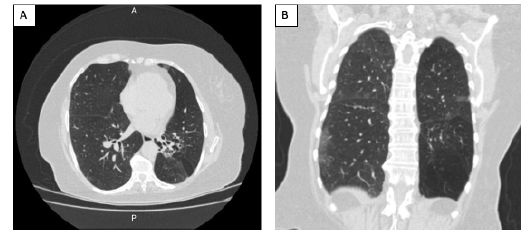

Como última opción, la paciente recibió una dosis de rituximab (1 g IV), consiguiendo estabilizar el recuento de plaquetas por encima de 50 000 plaq/uL a la tercera semana, dándose finalmente egreso al día 38 desde el ingreso; el plan ambulatorio fue repetir esta misma dosis cada 15 días por 2 dosis adicionales como terapia de mantenimiento (ver Figura 3). La TC torácica de seguimiento dos semanas posteriores a la extubación, antes del egreso hospitalario, informó de bandas pleuroparenquimatosas gruesas en relación con atelectasias que afectaban a ambos lóbulos inferiores y a la língula, sin derrame pleural, engrosamiento septal interlobulillar, opacidades reticulares de distribución peribroncovascular o subpleural ni bronquiectasias por tracción (ver Figura 4). Se resumen los medicamentos administrados durante la atención a la paciente, con sus respectivas dosis (ver Tabla 3). No hay registro del seguimiento por consulta externa de la paciente.

Figura 4 TC torácica de seguimiento A. vista axial. B. vista coronal. Sin infiltrados ni consolidaciones, sin derrame pleural; bandas pleuropa-renquimatosas gruesas en relación con la atelectasia que afectan a ambos lóbulos inferiores y a la língula. Los episodios repetidos pueden provocar neumonía organizativa, depósito de colágeno en las vías respiratorias pequeñas y fibrosis pulmonar.